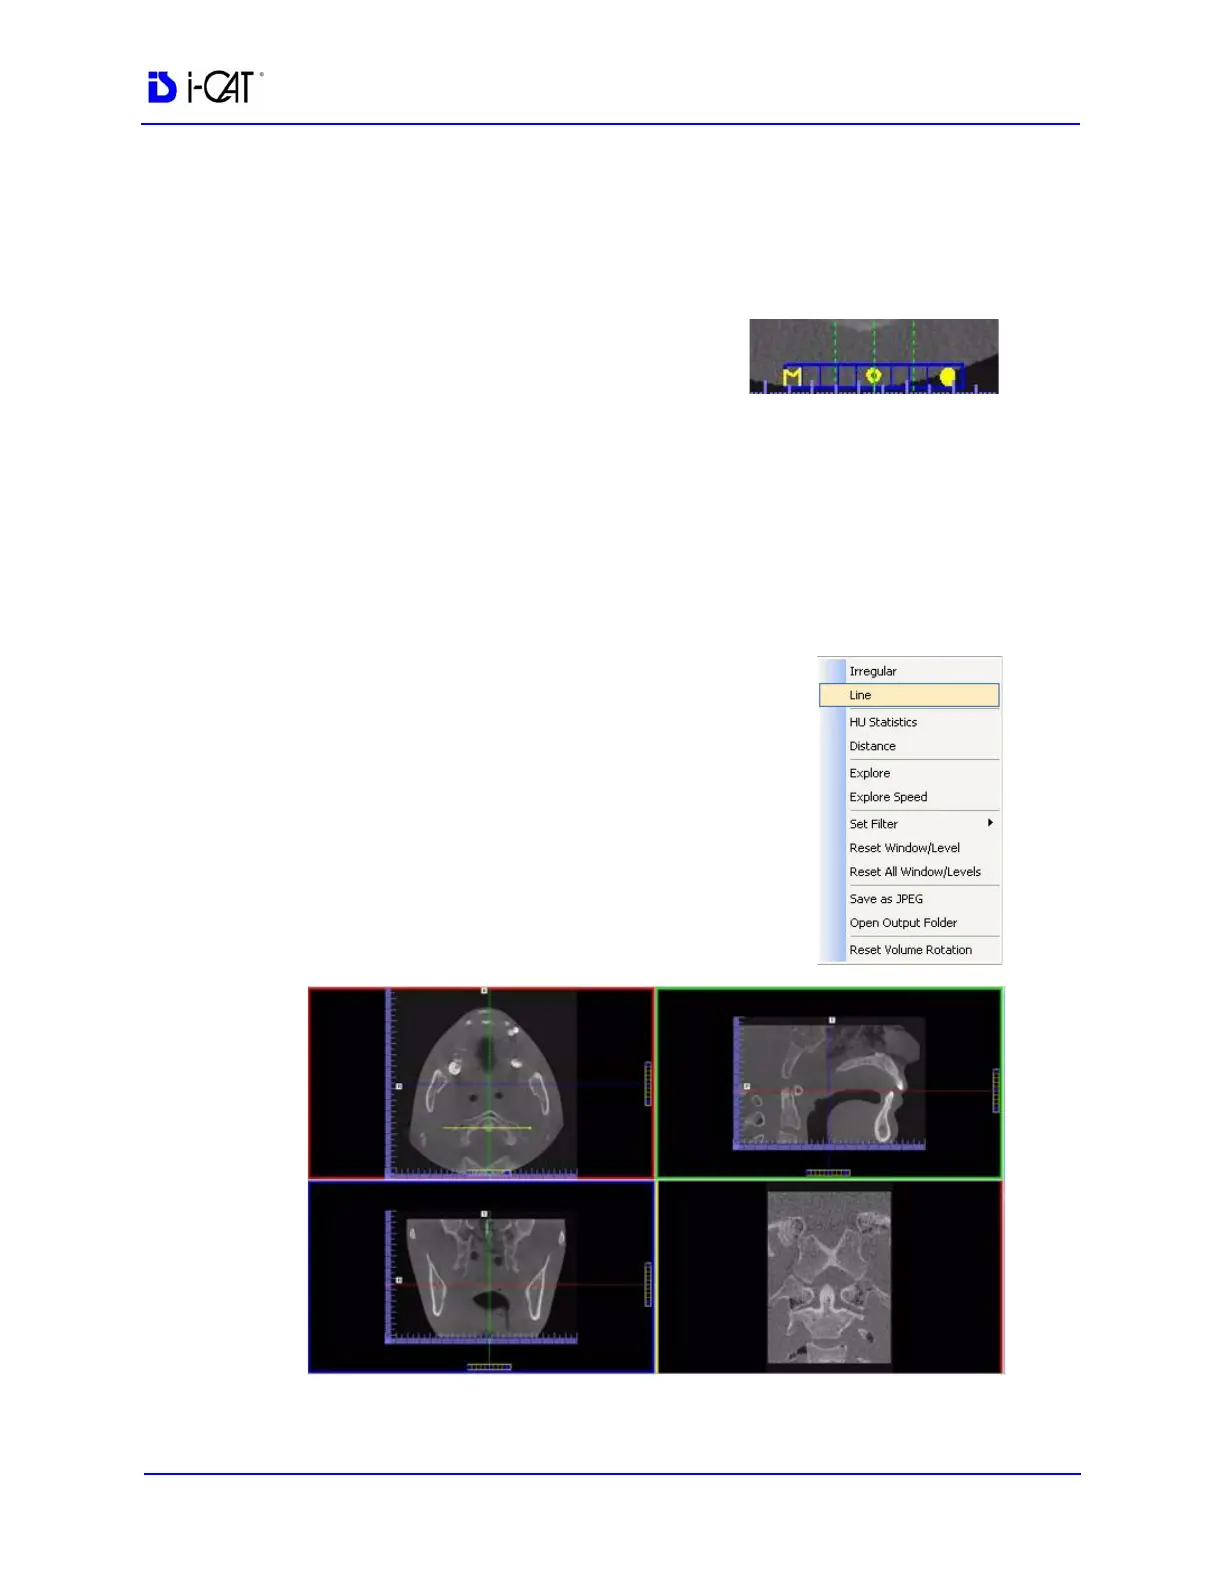

The MPR Screen allows scrolling through the Axial (upper left),

Sagittal (upper right), and Coronal (lower left) slices. The resulting

selections are displayed in the lower right view of the MPR Screen.

1. To view a linear slice, right click the

view and select Line.

A pointer cursor is displayed.

2. Drag to position the linear slice.

The resulting slice is displayed (lower right of the MPR Screen.)